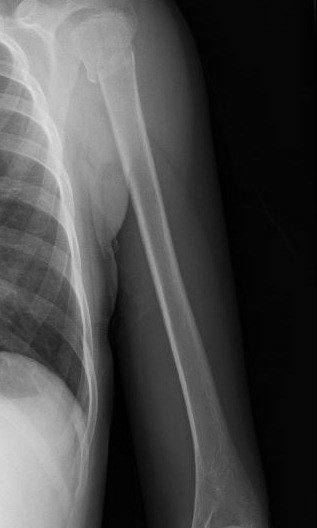

We headed to Urgent Doc thinking it would be faster than the E.R. They were all very careful and kind to her so I was very grateful. She got a couple x-rays and the doc came in telling us it was fractured in two places and a possible dislocated shoulder and it may require surgery. I was totally shocked at this point. “Surgery?? For a broke arm??” I said in my mind, “No! God I do not accept this man’s diagnosis! YOU are the great physician and YOU made this little body of Anna’s and YOU can fix it without surgery!” And that is just how I prayed! I started posting on Facebook and calling family to get a prayer chain started as we drove from Urgent Doc to Woodland Heights E.R. where the orthopedic doctor was on call.

anna arm

After a quick look at the x-rays the doctor came in and said that she only had one fracture up by the shoulder and no surgery was necessary! “Thank you Lord!” , I praised! He said these kinds of breaks heal just fine 90% of the time without surgery as long as she takes it easy. I told him, “I have full faith that it will heal and not need surgery!” Again, all the medical staff were super sweet to my baby girl.

Because of where the break was they could not put a cast on it, which disappointed her because she remembered some friends having a neon green cast and everyone signing it. All she got was a sling and a big ace bandaged so she will have to be very careful for a few weeks not to bump her arm.